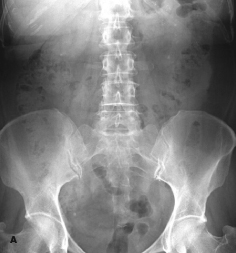

An abdominal radiograph (A) and a CT scan of the kidneys, ureters, and bladder (B) showed bilateral renal calcifications. On the right, the largest was 3 mm, and on the left, multiple punctate calcifications were evident. Urinalysis was positive for trace blood and trace leukocytes. The analysis of the stone revealed triamterene composition. The patient underwent successful placement of ureteral stents to help passage of the stones followed by lithotripsy.

Treatment consists of discontinuation of the medication and lithotripsy, because the calculi cannot be dissolved by pH manipulation.3 On plain radiographs, triamterene stones are—as in this case—faintly radio-paque and are less dense than calcium oxalate stones. They are more detectable on a CT scan of the kidneys, ureters, and bladder.